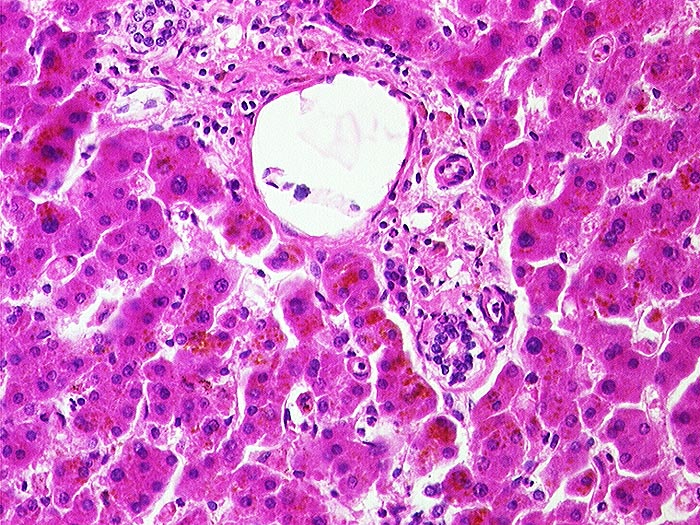

Lipofuszinose bei Phenacetinabusus

Artefakt / Fremdkörper / Pigment

Leber

Braunes Pigment in den Hepatozyten.

Diffuse Ablagerungen von Lipofuszinpigment in der Leber.

Phenacetinabusus.

Lipofuscinpigment kommt auch unabhängig von Phenacetinabusus im Alter vor. Makroskopisch braune Atrophie der Leber.